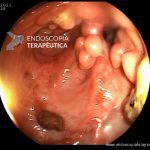

- Doença de Crohn em atividade moderada